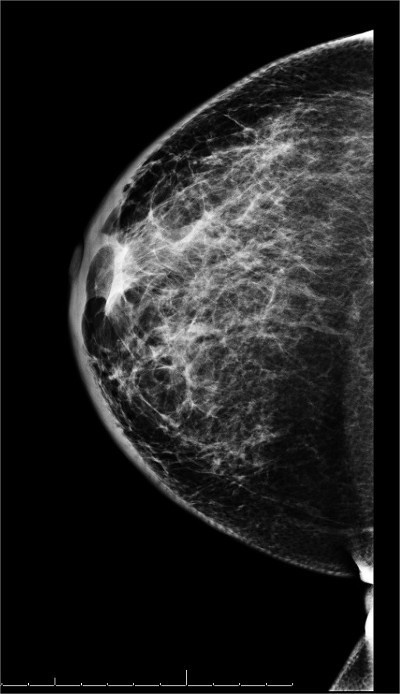

👉In addition to MRI and molecular imaging, both tomosynthesis and breast ultrasound are additional techniques for enhanced screening in patients with dense breasts.

👉Multiple studies have now shown significant benefits from the addition of tomosynthesis to conventional digital mammography alone in screening programs.

👉A prospective multicenter study compared tomosynthesis with bilateral physician hand-held ultrasound screening in 3231 asymptomatic patients with mammography-negative dense breasts.

– In all, 24 additional cancers were detected, 23 of which were invasive.

– Tomosynthesis detected 13 cancers, and ultrasound detected 23.

– These data suggest that even though tomosysthesis significantly increases the number of cancers found in dense breasts, in the hands of a skilled breast radiologist, ultrasound may be even better.